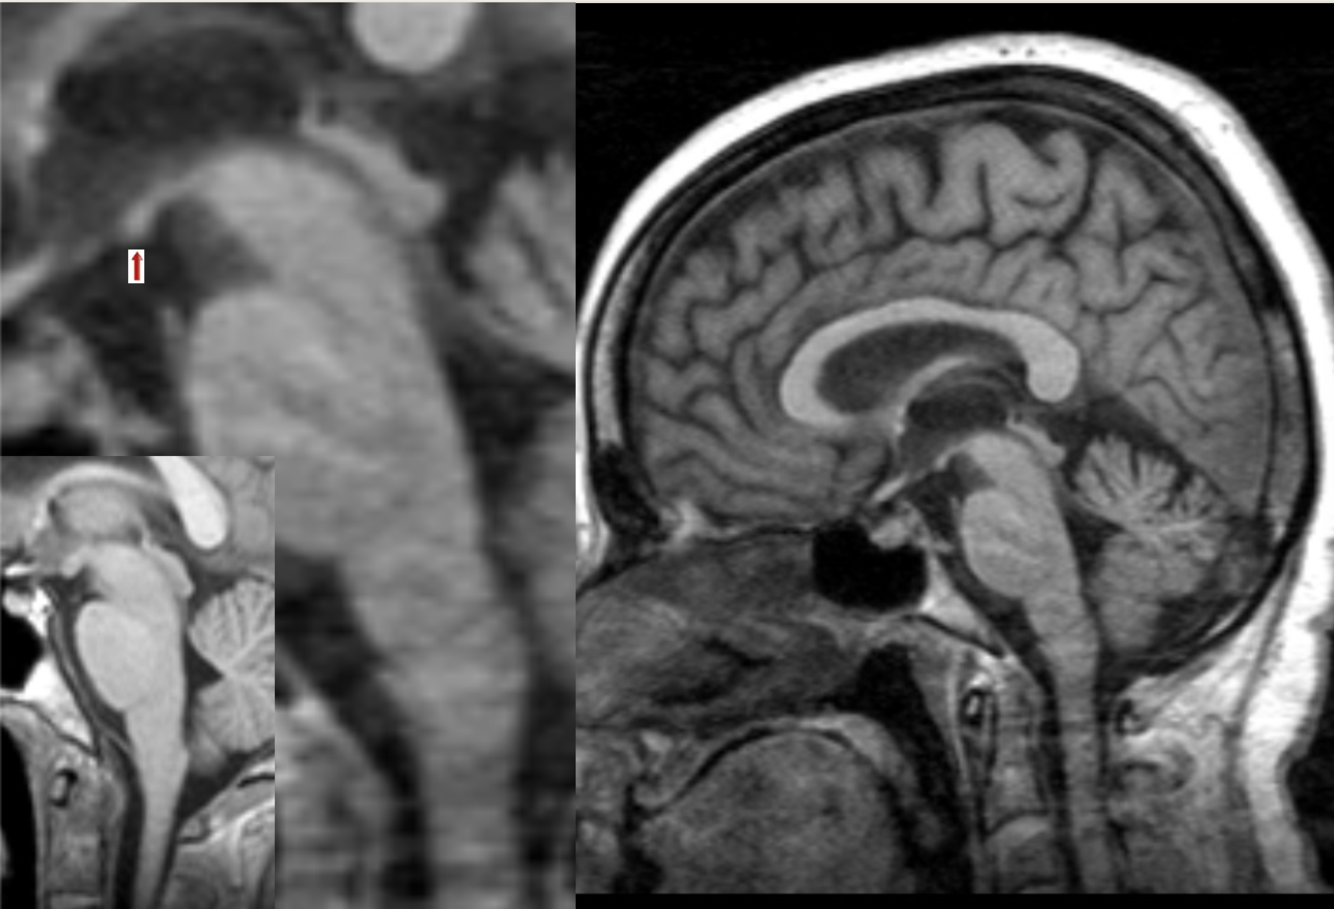

65 y/o alcoholic with confusion. The smaller, inset image is a normal MRI for comparison.

Wernicke’s encephalopathy